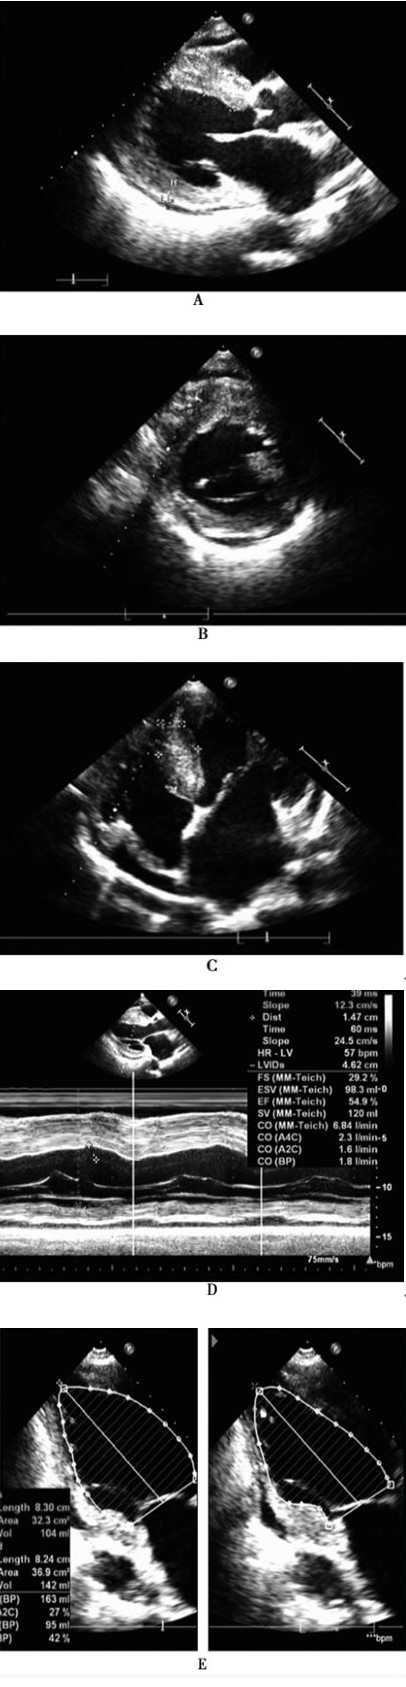

入院常规行超声心动图:左心室壁节段性室壁变薄、运动减低 (下壁中段至心尖段,后壁基底段至中段),符合急性下后壁心肌梗死超声改变;整个左心室壁明显非均匀性增厚、回声增强,最厚处位于前室间隔中下段厚度约25mm,前室间隔中段厚度19mm、基底段厚度18mm,后间隔中段厚度24mm、基底段厚度17mm、心尖段厚度13mm,增厚室壁回声粗糙,呈斑点样改变,心肌纹理排列紊乱,运动幅度正常;双心房、左心室增大伴少量主动脉瓣反流;左心室整体收缩功能轻度减低,左心室顺应功能减低,右心室舒张功能减低;心包积液 (少量),下腔静脉增宽、压力增高,心动过缓,符合非梗阻性肥厚型心肌病(双心室受累)超声改变(图3-1)。

图3-1 入院超声心动图 A:整个前室间隔、左心室后壁增厚(最厚处达2.5cm),心肌回声增强;B:左心室下壁变薄,余左心室壁基底段均明显增厚;C:后间隔明显向两侧增厚(最厚处达2.4cm),心肌回声增强;D:左心室后壁运动幅度明显减低,增厚率明显减低;E:双平面Simpson法显示左心室整体收缩功能轻度减低,左心室下壁中段至部分心尖段室壁变薄、三层结构消失,僵硬不动,室壁增厚率消失